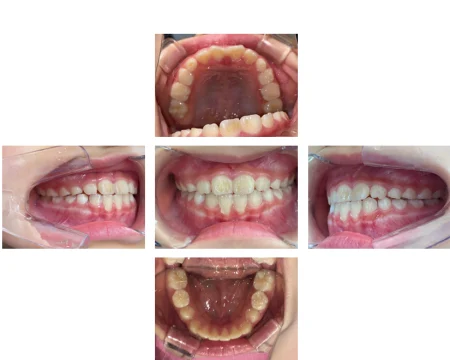

とてもきれいな歯並びになり、お母様もご本人様も大変満足されていました。

現在は歯並びをキープさせる「保定期間」に入っており、永久歯が完全に生え揃うまで今後は経過を見ていきます。